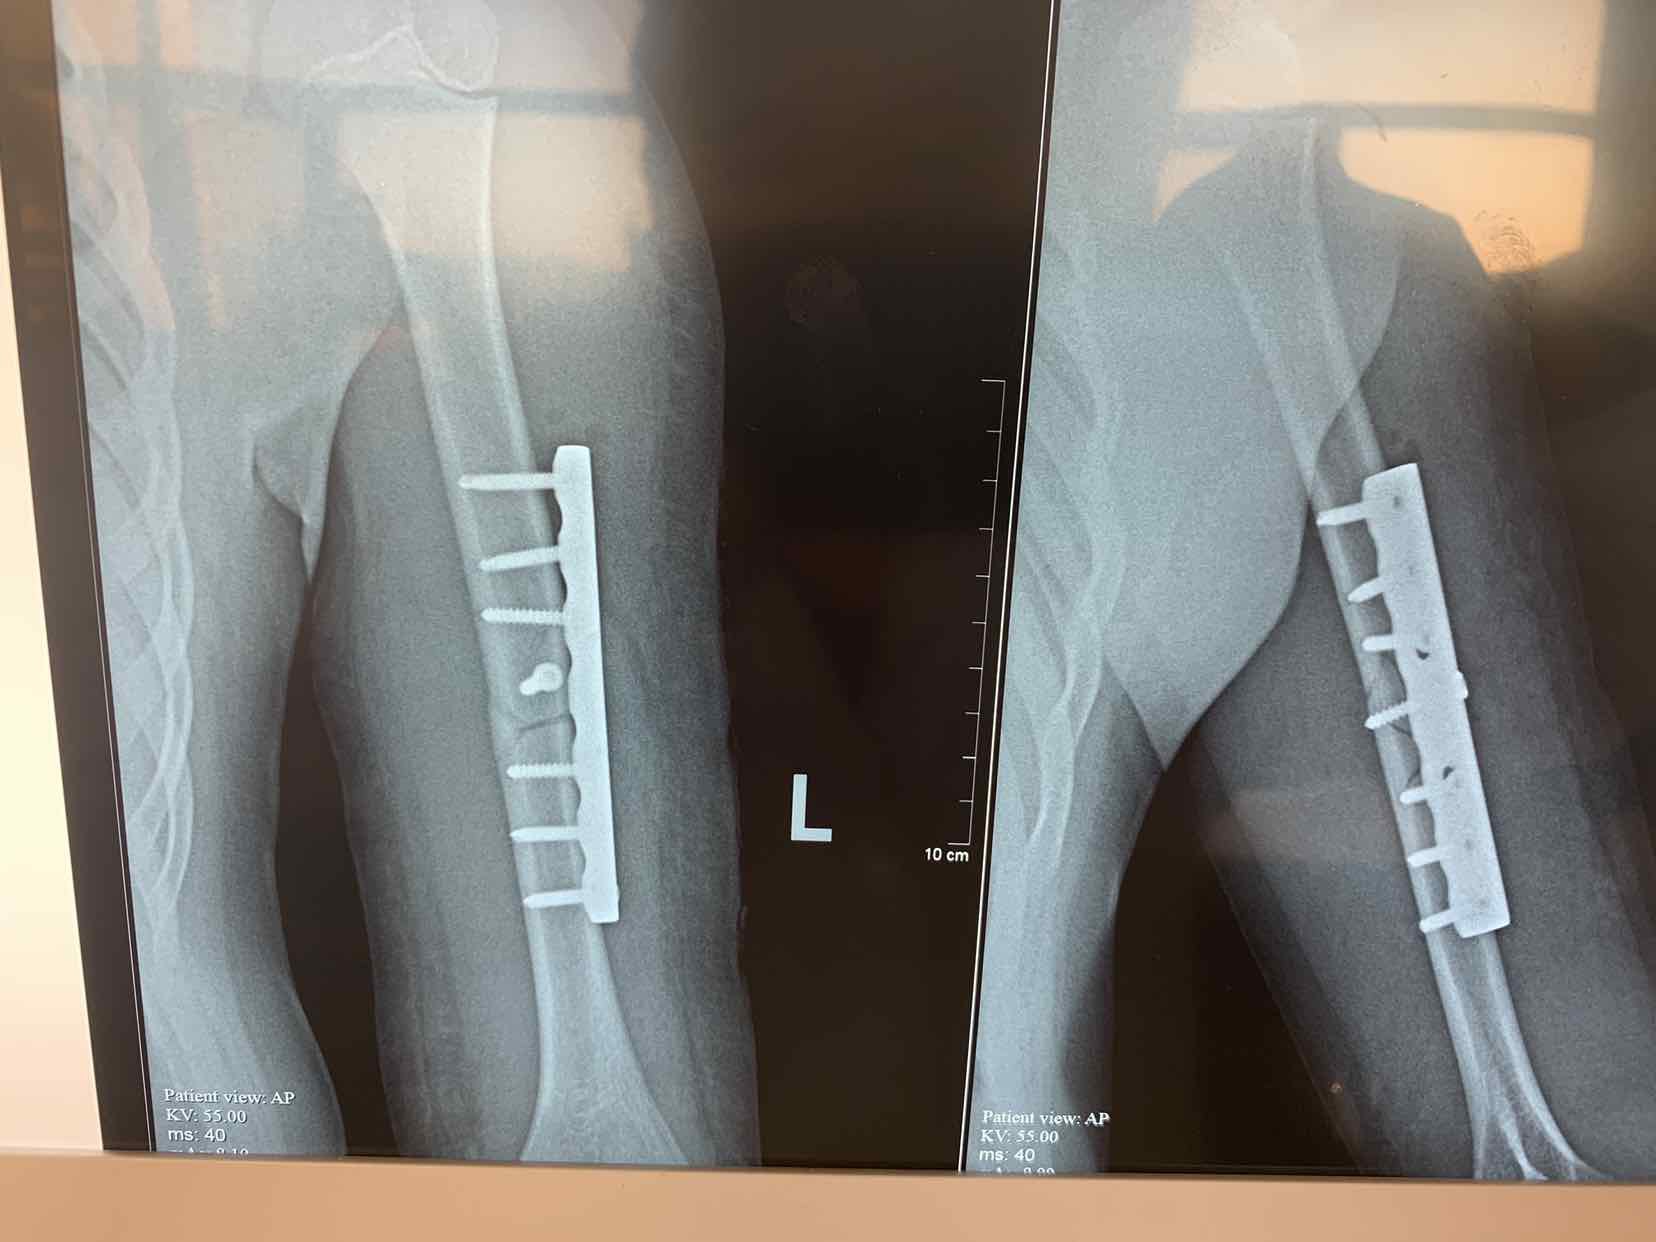

诊断为左侧肱骨中段骨折。全麻下行切开复位内固定术。术中局部应用拉力螺钉固定骨折端,安放六孔锁定钢板内固定,效果不错。术后早期就可以活动了。